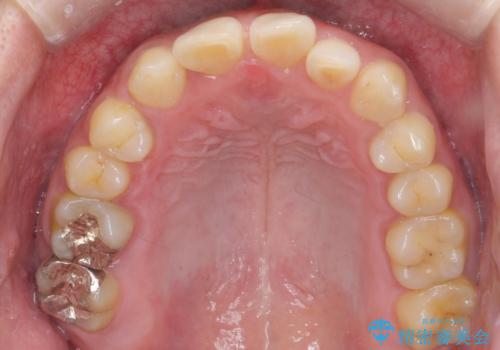

前歯のすき間 歯のがたつき

- 前歯のすき間とがたつきを主訴に来院。

右上の前歯は過去にがたつきがあったとのことで抜いてしまっていました。

歯の数を合わせるために、下の歯を1本抜いて矯正しています。

下の前歯を抜歯したことでブラックトライアングルができましたが、仕上げにIPRを加えることで目立たなくすることができました。